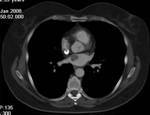

Methods: Twenty-two patients referred to our department with a suspected cardiac mass, previously detected by cardiac ultrasound, were evaluated by CT (12 patients) and MRI (4 patients). Six patients were examined by both modalities. In 2 cases of staging of a known primary neoplasm and one case of a suspected epicardiac lesion, positron emission tomography (PET-CT) was performed. The CT cardiac examinations were performed using a 16-slice multislice scanner with ECG gating. The MRI examination was performed on a 1.5 Tesla MRI scanner using an ECG-gated cardiac protocol and the PET-CT examination was performed on an integrated PET-CT four-slice scanner, using 370 mMBq of fluorodeoxyglucose.

Results: Twenty-two cardiac masses were successfully detected and their characteristics adequately delineated, including eight myxomas, one angiosarcoma, one ventricular lymphoma, one endocardiac metastasis, one epicardiac paraganglioma, and 10 cases of intracardiac thrombi.